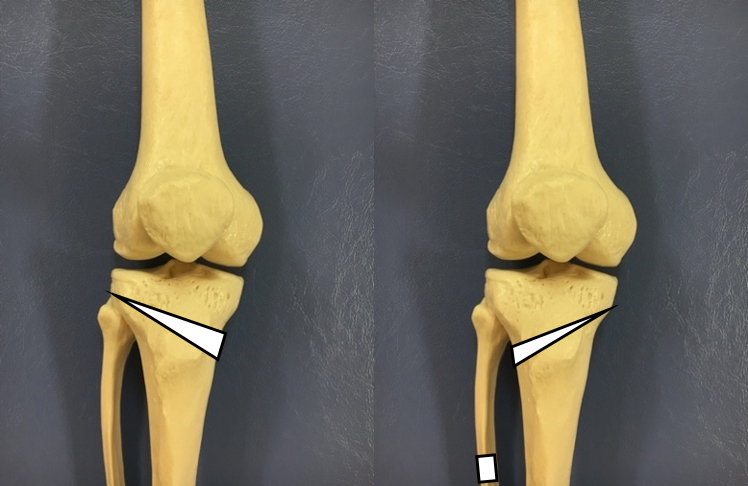

・脛骨高位骨切り術(HTO:Hight Tibial Osteotomy):(図3)

【図3】

左はOpen Wedge HTOおよびDTOの骨切り位置

右はHybrid Closed Wedge HTOの骨切り位置

脛骨と呼ばれるすねの骨を膝に近い位置で切り、変形を矯正する手術になります。HTOにはOpen Wedge HTOとHybrid Closed Wedge HTOがあります。Open Wedge HTOは、内側から外側に向かって脛骨を切り、人工骨を入れて変形を矯正する方法になります。Hybrid Closed Wedge HTOは、外側から内側に向かって脛骨を楔状に切り落として、変形を矯正する方法になります。Hybrid Closed Wedge HTOの場合、腓骨と呼ばれる脛骨に並走する骨も切り落とします。どちらの方法を用いるのかは、変形の程度によって選択されます。

・脛骨遠位粗面下骨切り術(DTO:Distal Tuberosity Osteotomy):(図4)

【図4】

左はOpen Wedge HTOの骨切り位置

右はDTOの骨切り位置

基本的にはOpen Wedge HTOと同様の手術になります。Open Wedge HTOの場合、脛骨粗面と呼ばれる膝蓋腱の付着部を遠位側に残すように骨切りされます。近年、この手術によって膝蓋骨の位置が変化することで、膝蓋大腿関節における関節症の発症リスクが高まる可能性が示されています。この解決策として誕生したのがDTOになります。DTOは従来のOpen Wedge HTOにおける脛骨粗面の骨切り方法を変更したものです。脛骨粗面を近位側に残すよう骨切りすることで、膝蓋骨の位置が変化せず、膝蓋大腿関節における関節症の発症予防になると考えられています。

一般的に、変形膝関節症による内反変形に対してはHTOまたはDTOが用いられ、外反変形に対してはDFOが用いられます(図5)。また、変形が高度の場合は、DLO(Double Level Osteotomy)と呼ばれる大腿骨と脛骨の両方の骨切りを行う手術も用いられます。